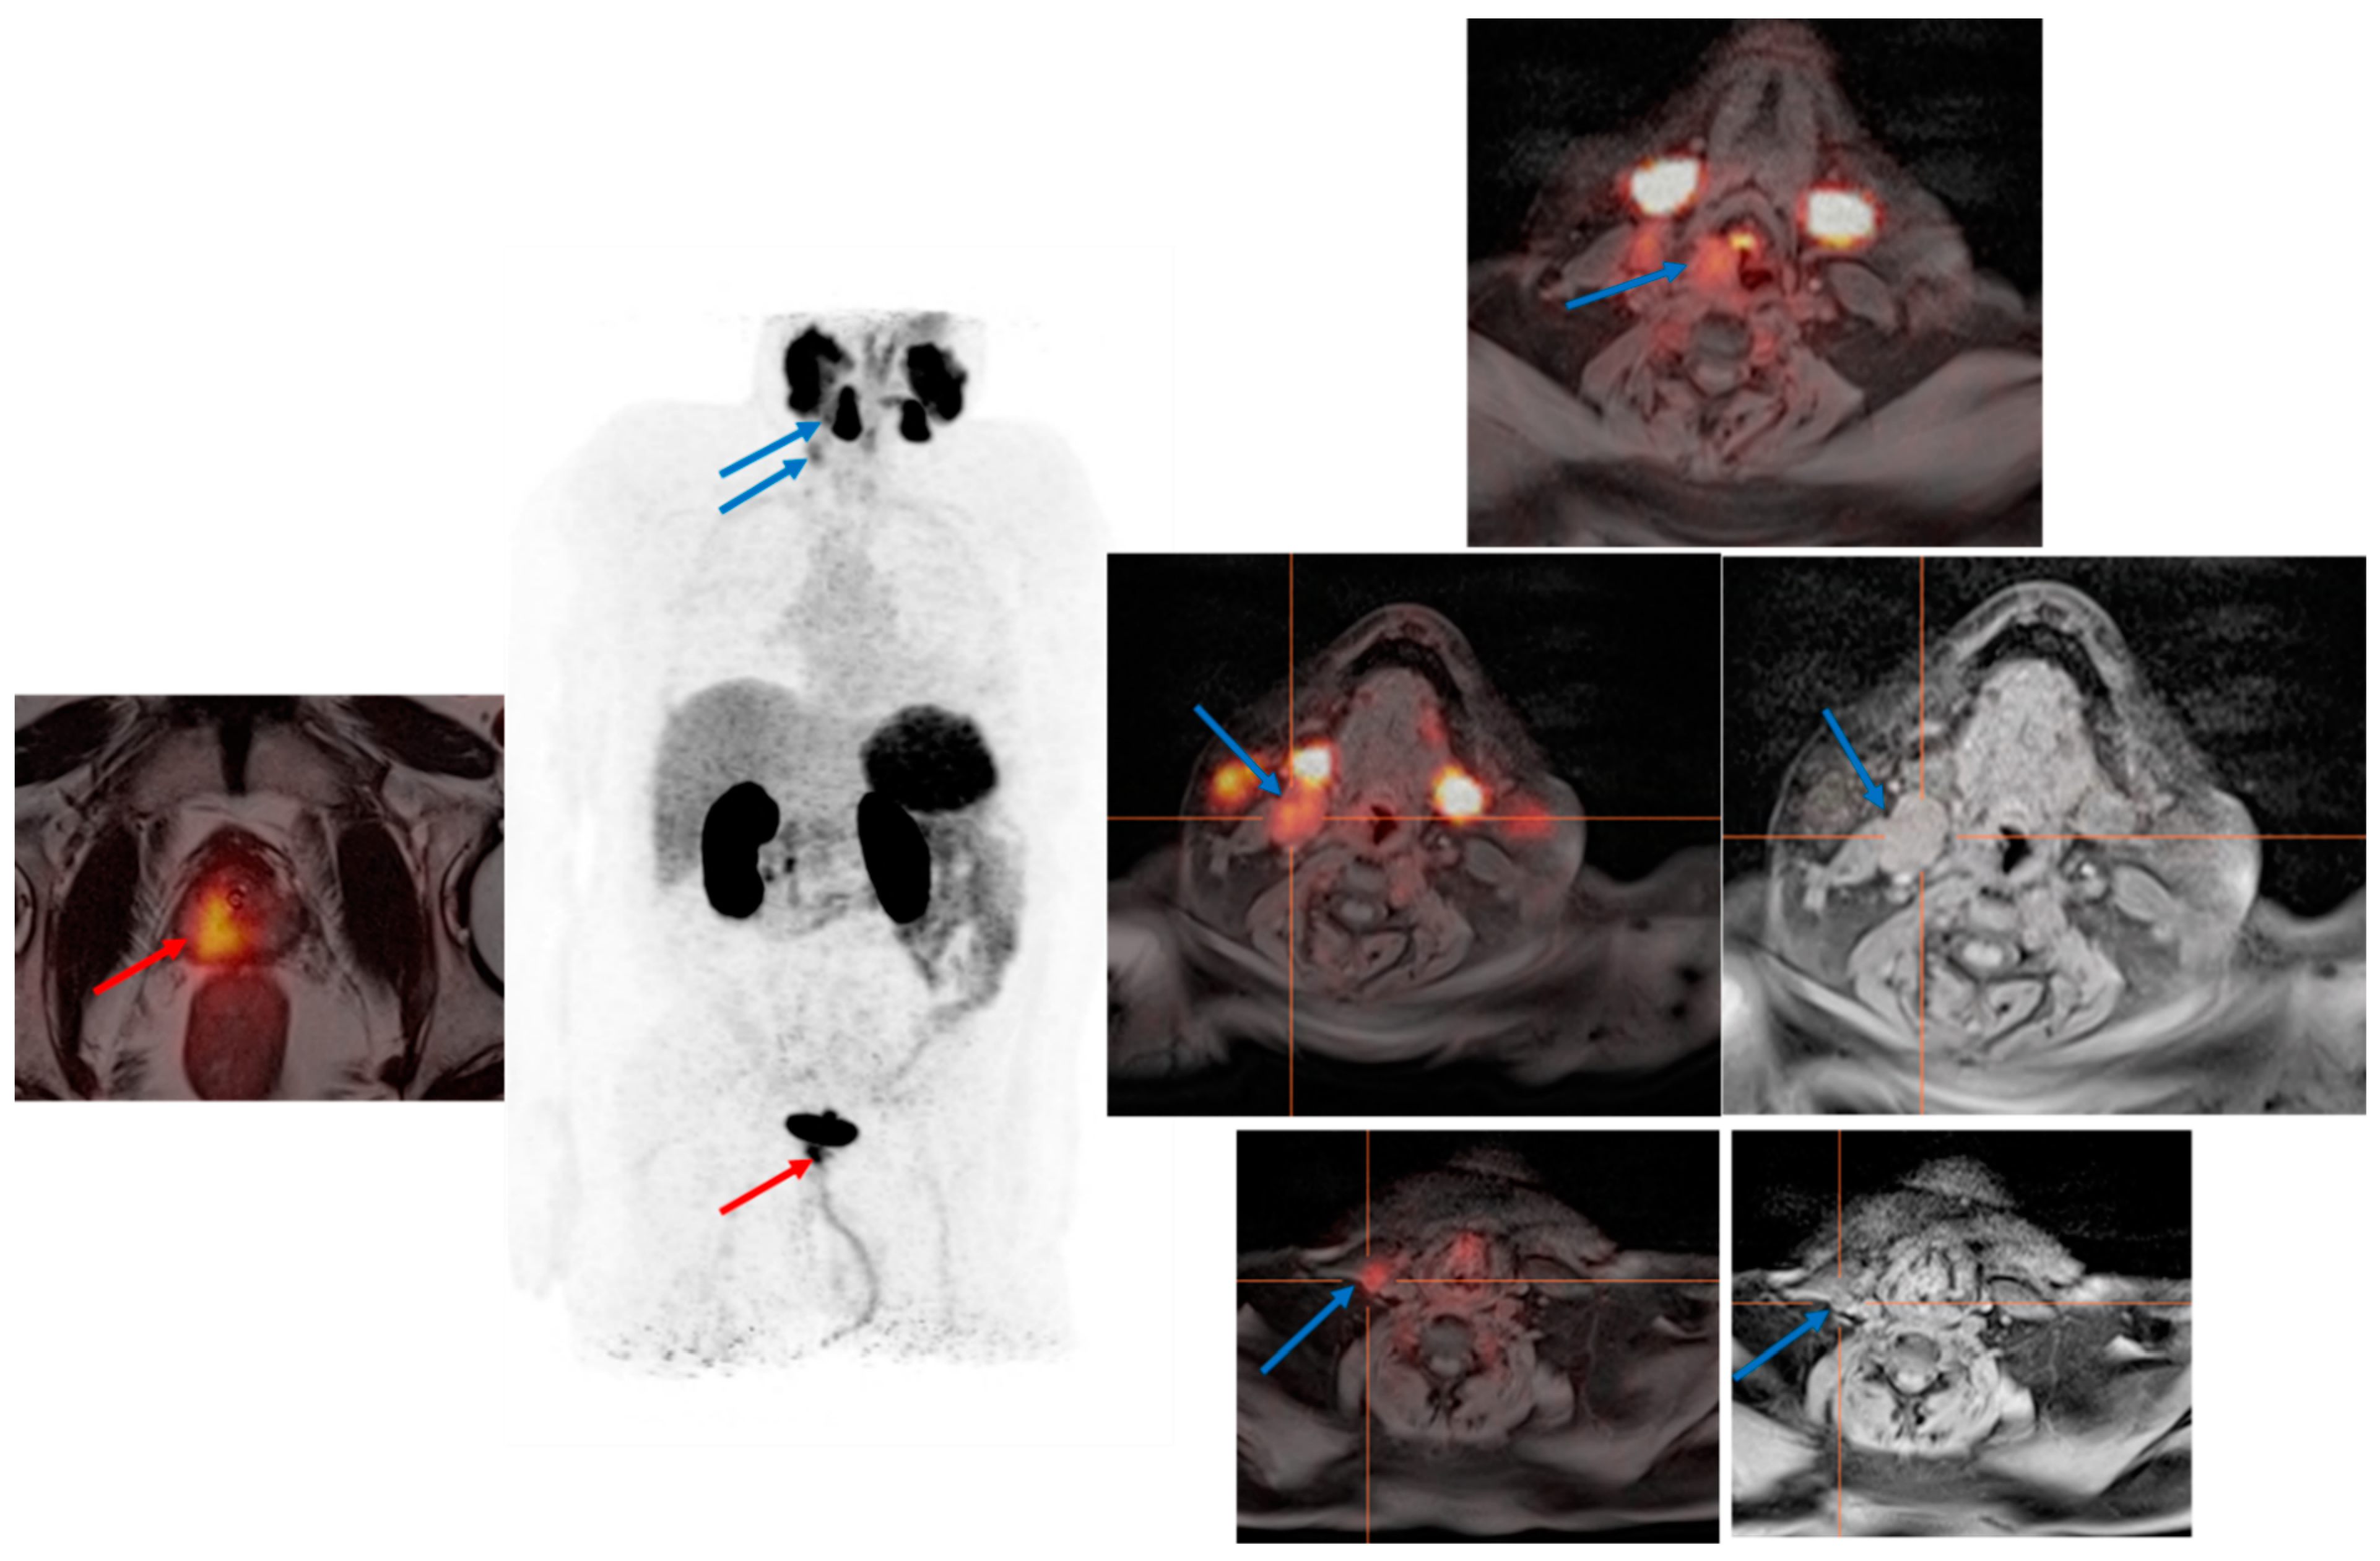

3.2. PSMA PET in Biochemical Recurrence PCa

3.3. Evaluation of PCa Patients for Possibility of PSMA Radioligand Therapies